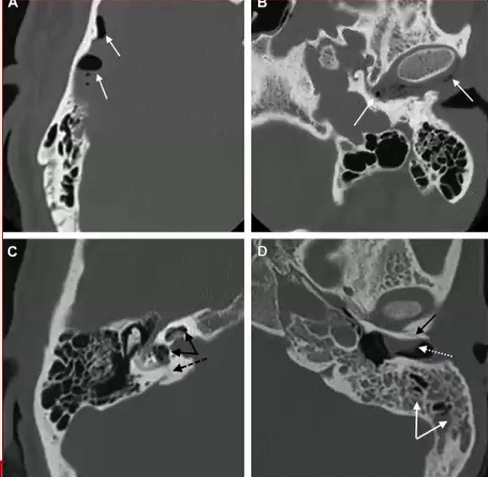

Cite o checklist de estruturas que devem ser avaliadas em uma tomografia de um trauma de osso temporal, como as abaixo.

A

• Localização e linha de fratura do osso temporal

• Capsula óptica e vestibulo

• Cadeia ossicular

• Canal e trajeto do facial

• Tégmen Timpânico

• Estruturas vasculares (carótida, seio sigmoide, transverso, bulbo da jugular).

Quais sinais INDIRETOS de trauma temporal são observados nas imagens abaixo, além da linha de fratura em si?

• Ar na região intracraniana, adjacente ao osso temporal

• Ar na articulação temporomandibular

• Pneumolabirinto

• Opacificação de células da mastóide

• Opacificação do CAE